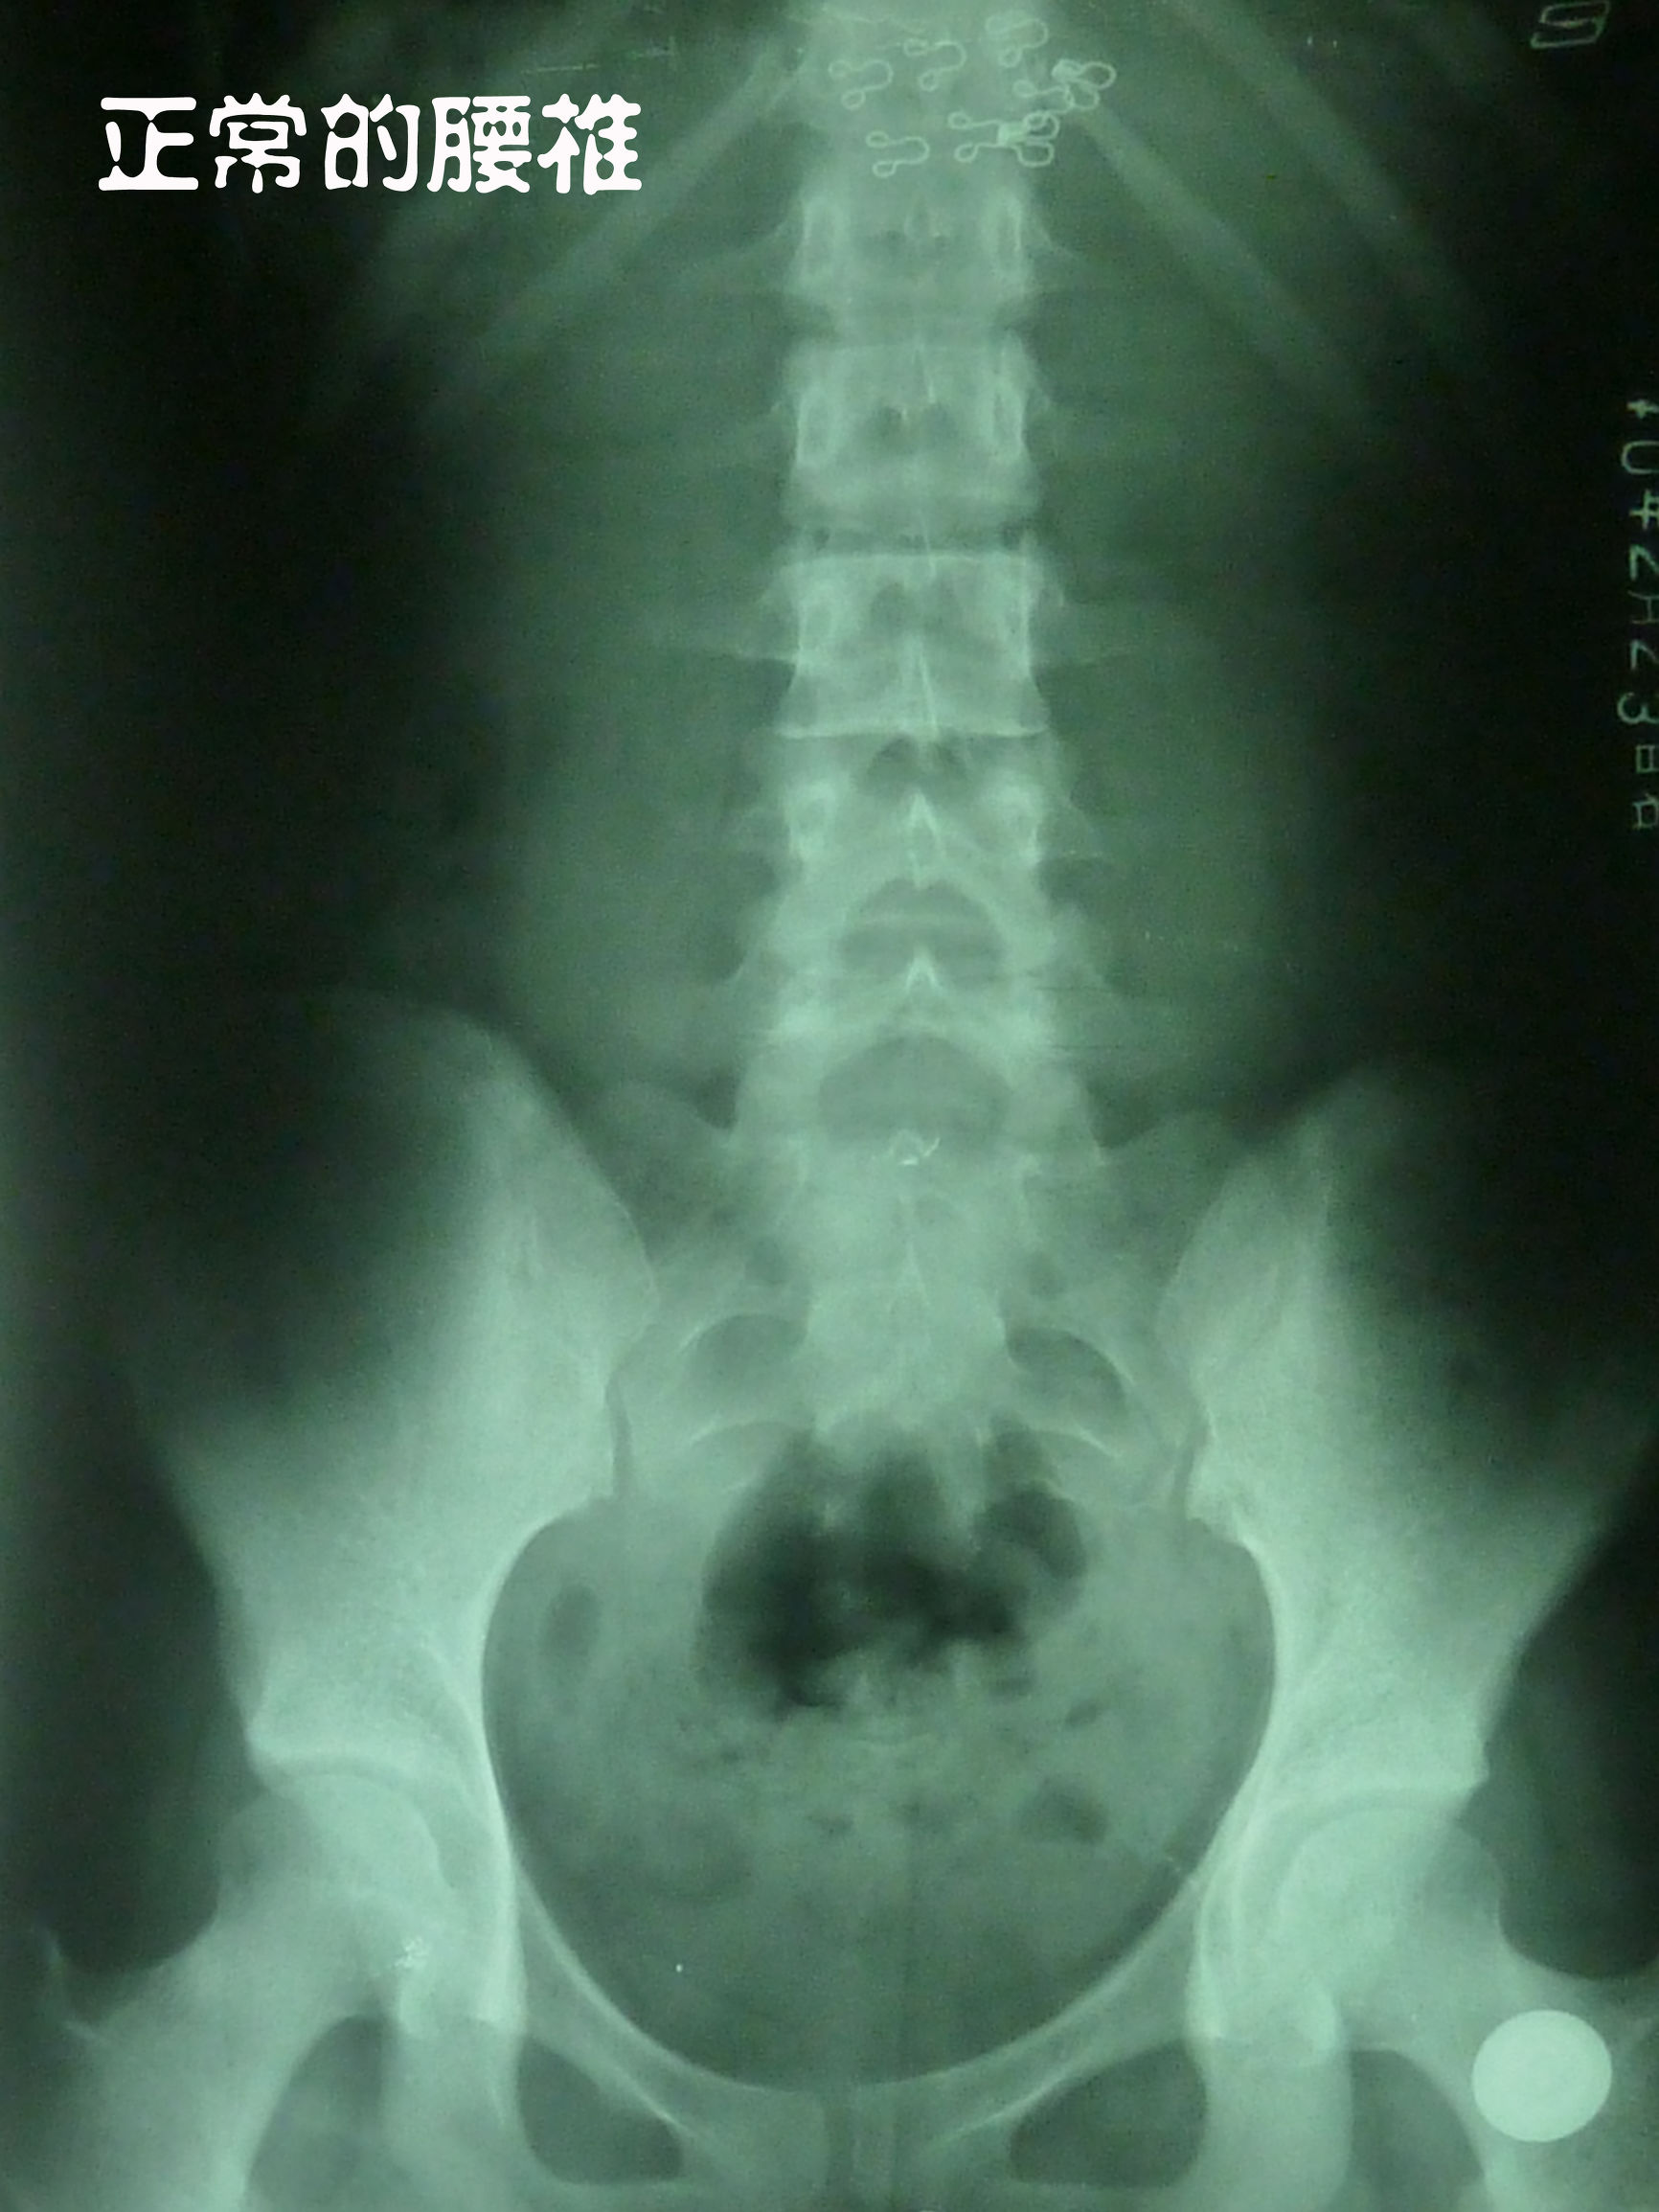

而腰椎结构好的人,一般就不容易得椎间盘突出,椎间盘受力均匀。